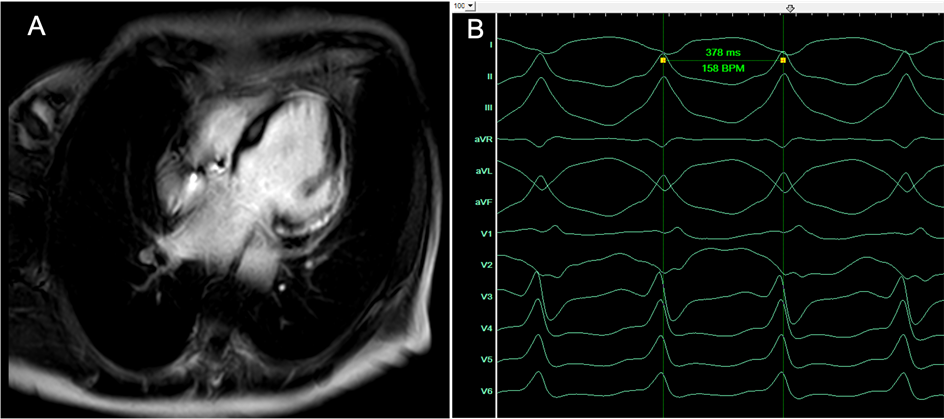

cMRT eines sub-epikardialen Substrats und EKG

Abbildung 1: Das cMRT zeigte ein großes sub-epikardiales Substrat mit später Gadolinium-Anreicherung (late enhancement) über der gesamten lateralen Wand des LV (A). (B) 12-Kanal-EKG der induzierten VT mit einer Zykluslänge von 378 ms bei superiorer Achse und breitem QRS-Komplex.